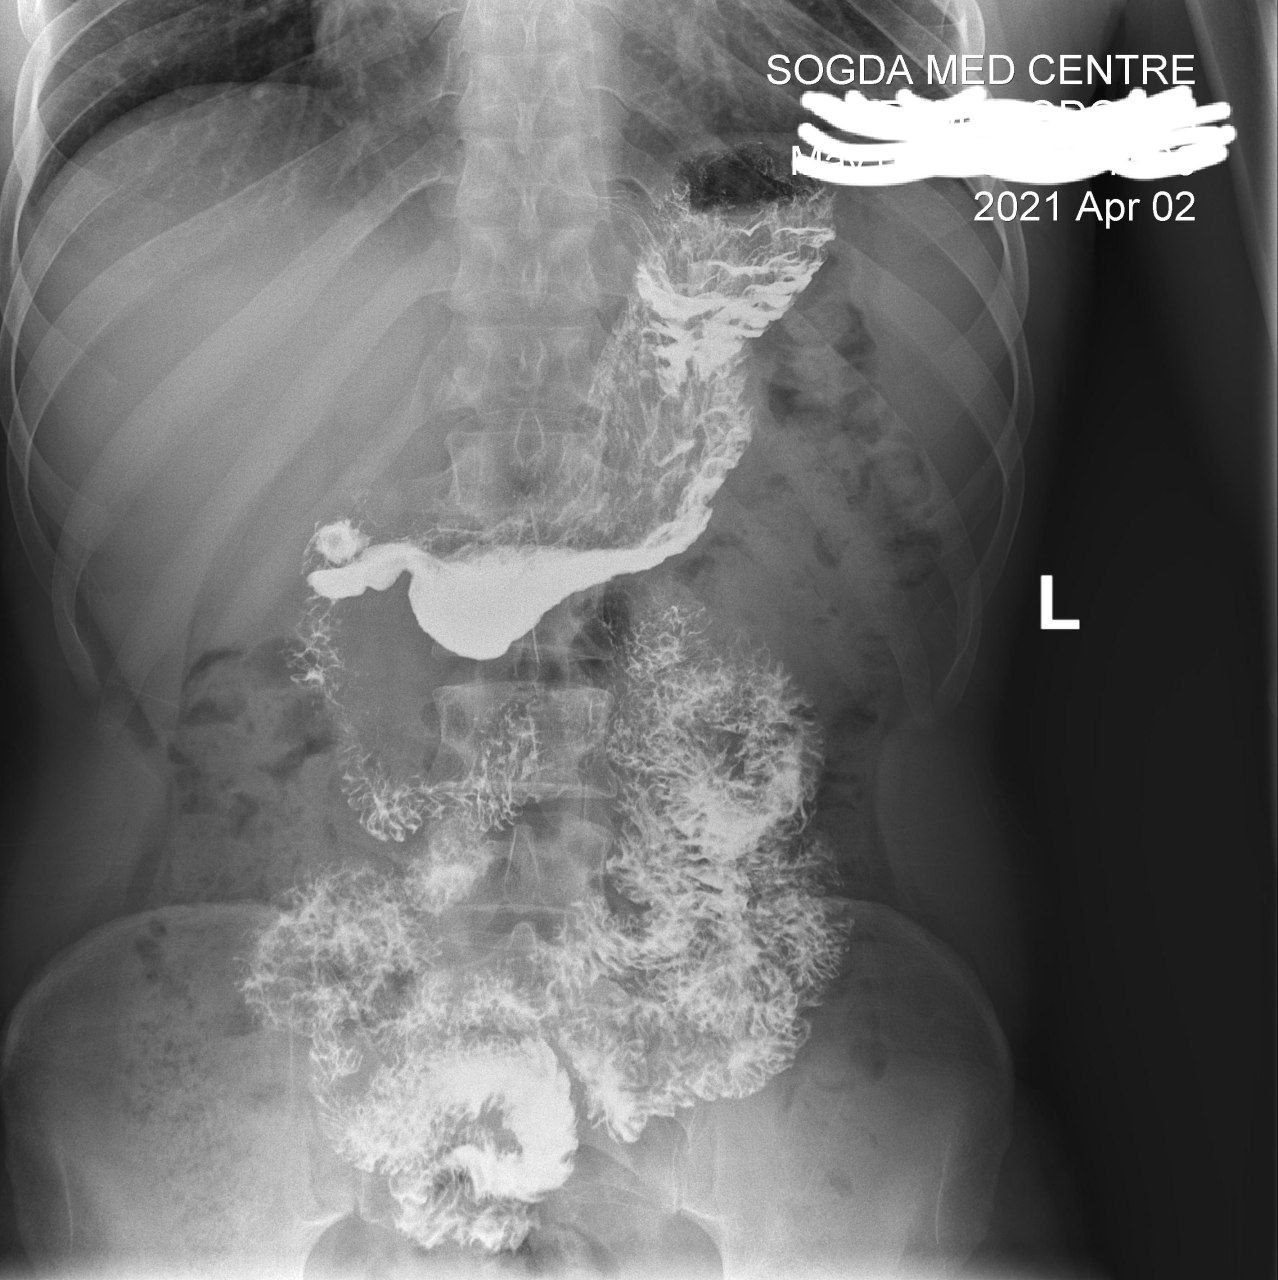

Ирига уже другая поциентка безпокоит запор

Долихосигма . Хронический колит

Нет ни того ,ни признаков другого

На таких исследованиях обычно ищут органическую патологию, а не всякую ерунду. Раз Вы утверждает ,что здесь какой то колит, то каковы его признаки?

Есть признаки долихи и колита

Потому что зделали колоноскапию 100% подтвердил